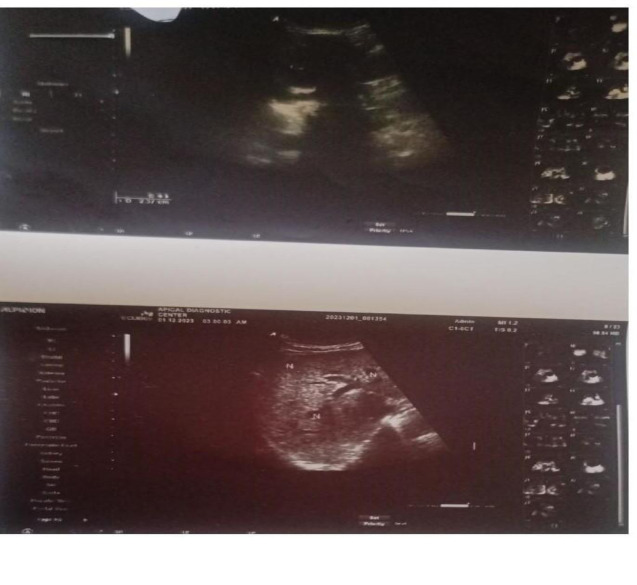

晚期慢性肝病常并发肝性脑病(HE)、肝肾综合征和自发性细菌性腹膜炎;预后不良的预测因子显著降低生存率。虽然原位肝移植(OLT)仍然是最终的治疗方法,但在资源有限的情况下往往无法获得。我们提出的情况下,一个70岁的退休医院服务员与高血压谁发展代偿性肝硬化继发慢性丙型肝炎病毒HCV感染。她表现为门脉高压、4级HE、肝肾综合征和自发性细菌性腹膜炎。她在3至4年级继续学习了大约三个月,在2-3年级继续学习了两个月。尽管存在严重的肝脏失代偿,终末期肝病模型-钠(MELD-Na)评分为48分(表明71%的三个月死亡率),Child-Pugh评分为15分(C类),但她对强化保守治疗反应显著。经过六个月的住院治疗,包括直接抗病毒治疗、抗衰竭治疗和癫痫发作治疗,她从肝性昏迷中恢复过来。她接受了六个月的直接抗病毒药物daclatasvir和sofosbuvir疗程,并取得了持续的病毒学应答。六年半后,她的健康状况良好,保持认知能力,血压正常,并每年接受肝细胞癌监测。该病例强调了DAAs在改善严重失代偿的hcv相关肝硬化患者的生存方面的变革性潜力。它强调了在资源匮乏的环境中,在肝移植不可行的地方,需要扩大daa的获取和补贴,并强调了积极的、支持性的管理在弥合治疗差距方面的作用。

Advanced chronic liver disease is frequently complicated by hepatic encephalopathy (HE), hepatorenal syndrome, and spontaneous bacterial peritonitis; predictors of poor prognosis that significantly reduce survival. While orthotopic liver transplantation (OLT) remains the definitive treatment, it is often inaccessible in resource-limited settings. We present the case of a 70-year-old retired hospital attendant with hypertension who developed decompensated liver cirrhosis secondary to chronic hepatitis C virus HCV infection. She presented with portal hypertension, grade 4 HE, hepatorenal syndrome, and spontaneous bacterial peritonitis. She remained in grade 3 to 4 HE for approximately three months and in grade 2-3 HE for an additional two months. Despite profound hepatic decompensation and a high Model for End-Stage Liver Disease-Sodium (MELD-Na) score of 48 (indicating a 71% three-month mortality) and a Child-Pugh score of 15 (Class C), she responded remarkably to intensive conservative management. After six months of inpatient care, which included direct-acting antiviral therapy, anti-failure therapy, and seizure management, she recovered from hepatic coma. She received a six-month course of direct-acting antivirals (DAAs)daclatasvir and sofosbuvir and achieved sustained virologic response. Over six and a half years later, she remains in good health with preserved cognition and normal blood pressure and has been under annual surveillance for hepatocellular carcinoma. This case underscores the transformative potential of DAAs in improving survival even among severely decompensated HCV-related cirrhotic patients. It highlights the need for expanded access and subsidization of DAAs in low-resource settings, where liver transplantation is not feasible, and emphasizes the role of aggressive, supportive management in bridging the treatment gap.